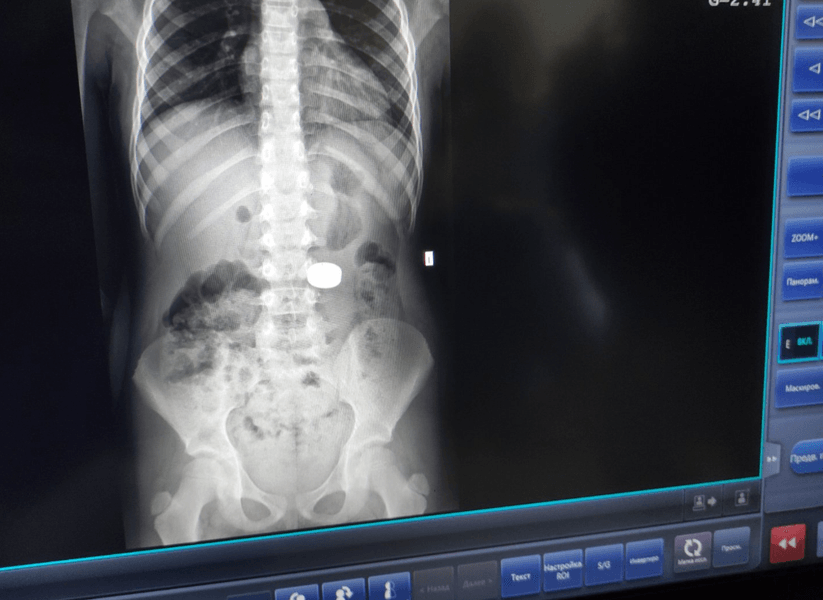

Зі шлунка 7-річної дівчинки дістали два магніти | Фото: Західноукраїнський спеціалізований дитячий медичний центр

Зі шлунка 7-річної дівчинки львівські лікарі дістали два магніти великого діаметра. Про це повідомили у пресслужбі Західноукраїнського спеціалізованого дитячого медичного центру у Facebook.

Мамі вона сама розповіла, що проковтнула магніти. Батьки звернулись у районну лікарню міста Миколаїв, що у Львівській області. Дитині зробили рентгенографію, і скерували у Центр.

Додаткові обстеження визначили точне розташування стороннього тіла й дали змогу дізнатись, чи не виникли згодом ускладнення. Лікар-ендоскопіст Олег Кочеркевич переконаний, що певним чином дитині пощастило, оскільки ці предмети були склеєні між собою й одним конгломератом впали у шлунок.

"Під їхньою вагою шлунок опустився до рівня тазових кісток", – розповів фахівець.

З його слів, спочатку візуально вони локалізувались у кишківнику. Згодом пацієнтці провели додаткове рентгенодослідження. Медики визначили, що сторонні тіла ще у шлунку, тож можна видалити їх ендоскопічно.